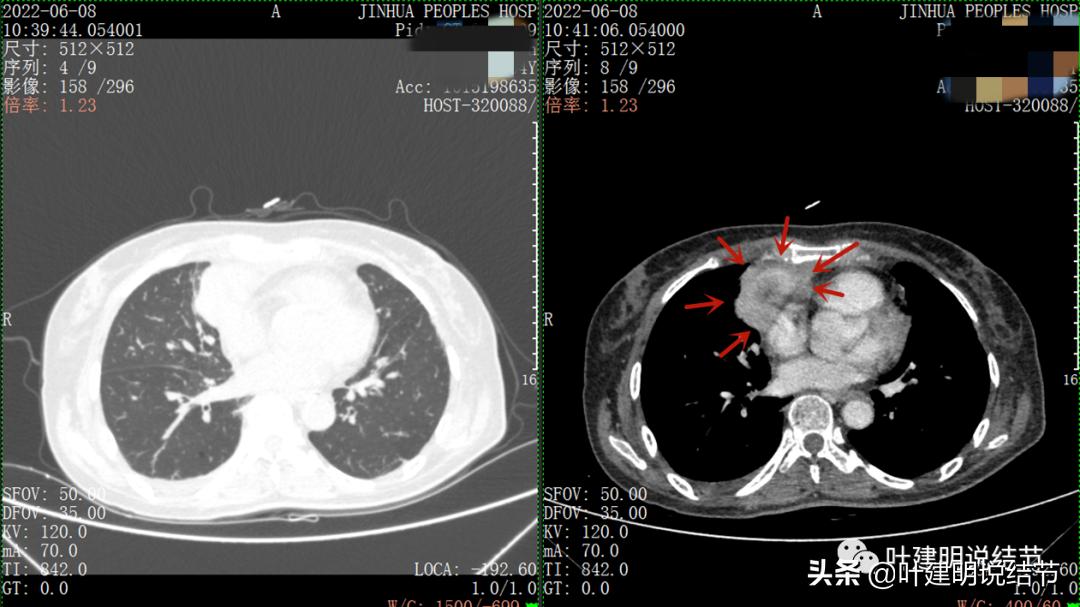

以下图片左侧是肺窗,右侧是纵隔窗。红色箭头示病灶,桔色箭头示无名静脉,黄色箭头示支气管,砖色箭头示上腔静脉,蓝色箭头示主动脉,紫色箭头示肺动脉。

病灶纵隔胸膜侧非常光滑,说明来源于纵隔

粉色箭头示淋巴结可能